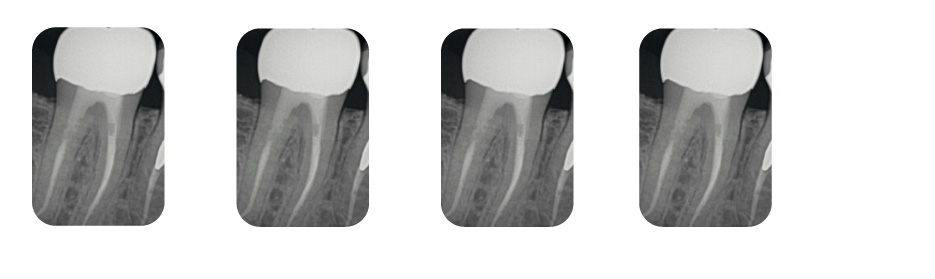

Fig. 12

Retraitement conservateur formé jusqu’à Shap-Y2